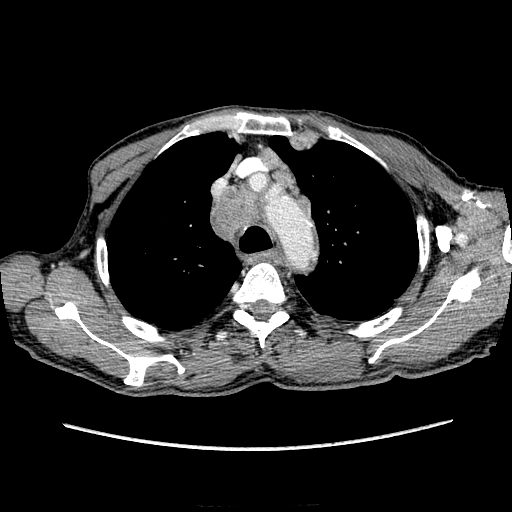

Печень. Процесс в средостении, бр.пол., забр.пр-ве. МСКТ.

Здравствуйте, коллеги! Мужчина около 70 лет. Жалобы: слабость, утомляемость около 3х месяцев, чувство тяжести на желудке после еды. Анамнез: онко не было. С вышеописанными жалобами обратился ко врачу, сделали ФГЭДС - признаки гастродуоденита, по биопсии - N. В течение 2х последних недель существенно похудел и начал желтеть. Выполнена МСКТ

Вероятно ГЦР, со всеми последствиями.

+1. А вот образование средостения к чему отнести?

Вероятно метастазы

А как насчет холангиокарциномы с тромбозом воротной вены и мтс в средостение, лимфоузлы брюшной полости и забрюшинного пр-ва?

Я - за.

Внимательно пересмотрел, признаков характерных для ГЦР не нашел (кроме тромбоза). Согласен с холангиокарциномой, ещё бы отсроченную фазу, для печени минут через 12-15 .